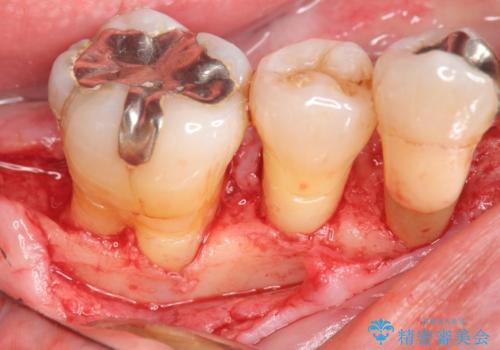

骨吸収の進行している右下臼歯部に、再生療法(骨を増やす手術))を行いました。

再生療法から1年後、リエントリー手術により骨の再生を確認し、骨外科処置(骨を平らにして歯周ポケットの根本的な改善を図る処置)を行いました。